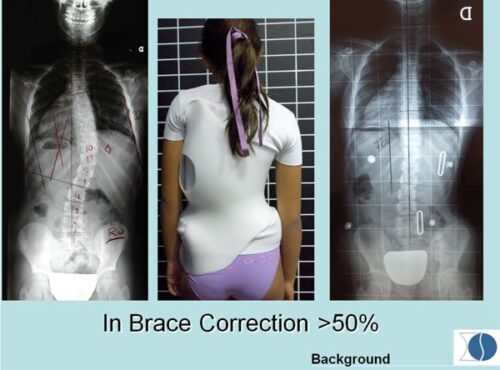

1. درجة التصحيح داخل الحزام (In-brace Correction)

أحد أقوى المؤشرات على نجاح العلاج هو مدى تحسن زاوية كوب أثناء ارتداء الحزام مباشرة.

فكلما كانت زاوية الانحناء داخل الحزام أصغر، زادت فرصة السيطرة على الجنف على المدى الطويل.

بعبارة بسيطة:

إذا لاحظ الطبيب تحسنًا واضحًا في الأشعة داخل الحزام، فذلك مؤشر إيجابي قوي للأهل.

هل تصميم حزام اعوجاج العمود الفقري نفسه يؤثر على النتيجة؟

الحزام الفعّال هو الذي:

يحافظ على التقوس الطبيعي للظهر

يتكيف مع شكل القفص الصدري

لا يسبب ضغطًا مفرطًا يعيق الالتزام

لذلك، الأحزمة المصممة خصيصًا بناءً على التحليل ثلاثي الأبعاد تحقق نتائج أفضل من الأحزمة التقليدية العامة.